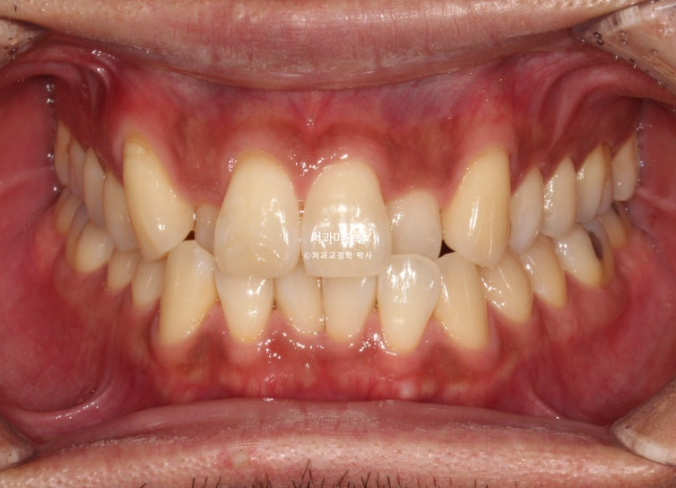

덧니가 있고 위아래 치아 중심선이 어긋나 있습니다.

치아중심선이 어긋나 있는 것은 아래턱 비대칭이 있기 때문입니다.

그에 비해 뒤쪽 어금니 교합은 좋은 편 입니다.